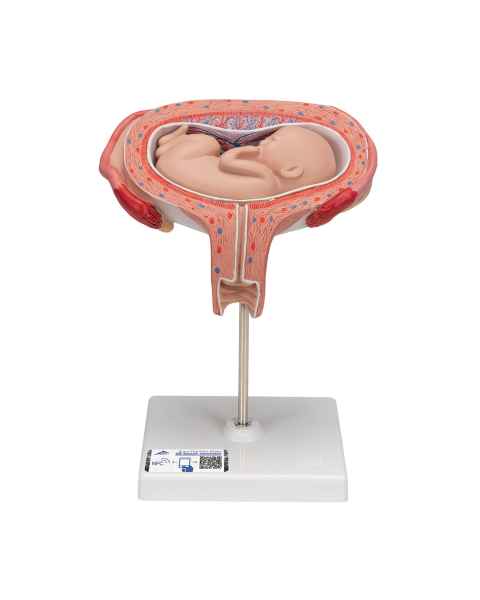

Female anatomical models are an ideal teaching aid to help educate both students and patients. Our extensive selection of female anatomy models includes female pelvic models, pregnancy series models, pelvis skeleton models, delivery/childbirth simulators, clinical breast trainers and self-exam models, uterus/ovary models, and more. Teaching simulators and self-exam models are excellent for educating students and patient education.

For example, the Wearable Breast Self-Exam Model can be easily worn, in order to better train and practice breast self-examination. Our line of prevention and detection models includes the Realistic Left Breast Model, Uterus/Ovary Model with Pathologies, Model of the Female Breast, and the Clinical Breast Trainer. Obstetricians will benefit from owning female anatomy figures of uteri and pelvises with fetuses inside, as well as sets of models that demonstrate the stages of fertilization. Women, particularly first-time mothers, will appreciate having a female education model that clearly illustrates the pregnancy process and what exactly is occurring inside of their body.